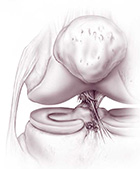

Il legamento crociato anteriore non può essere suturato; è necessario ricostruirlo utilizzando innesti tendinei che fungono da impalcatura su cui si formerà un neo-legamento. Gli innesti autologhi (prelevati dal paziente stesso) più frequentemente utilizzati sono il tendine rotuleo e i tendini flessori del ginocchio (gracile e semitendinoso). Si possono eventualmente utilizzare anche innesti omologhi (da cadavere).

La tecnica chirurgica prevede la preparazione di 2 tunnel ossei (tibiale e femorale) entro cui viene fatto passare il trapianto debitamente preparato che verrà poi fissato con viti o pin (metallici o di materiale riassorbibile).